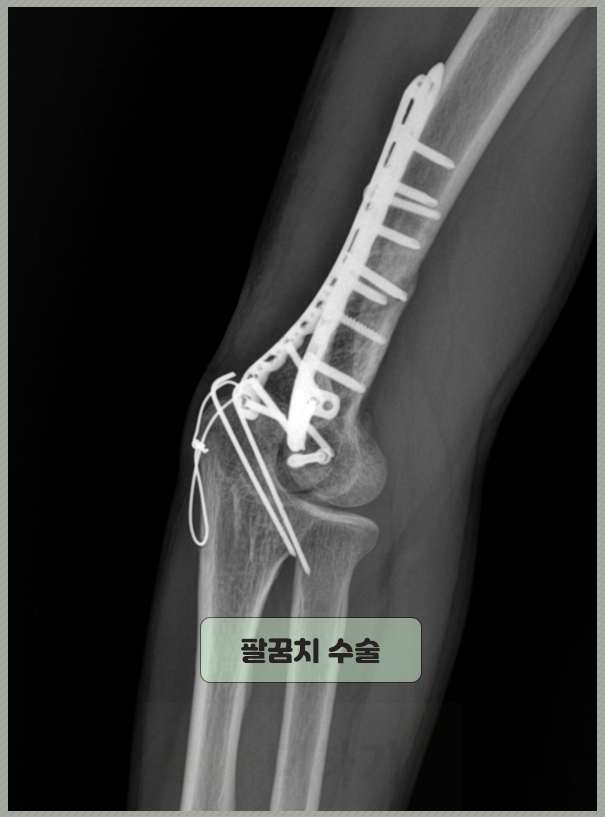

▶▶▷ 40대 후반 김 ** 님(경기) 사례자분은 운동 중에 다치셨고, 팔꿈치 골절 진단을 받으셨습니다. 정확한 진단명은 다음과 같으며 위팔뼈인 상완골 아랫부분이 손상되었습니다. Lt. distal humerus intraarticular comm. fx. 좌측 원위부 상완골 관절 내 분쇄 골절 뼈가 세 조각 이상 조각나듯 부러지고 부러진 부분이 팔꿈치 관절안까지 침범한 상태였습니다. 따라서 수술 치료를 시행 받으셨어요. 금속판, 나사 핀 등을 이용해 뼛조각을 정밀하게 고정했습니다.